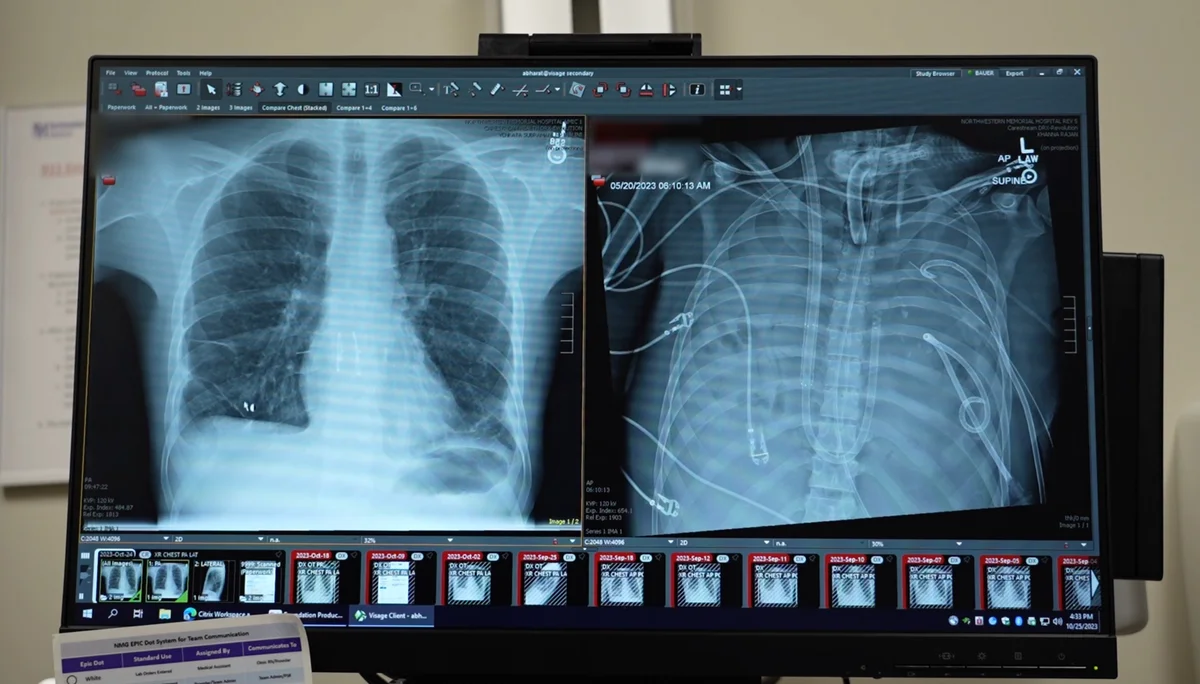

Cu toate acestea, medicii au decis recoltarea unei probe de țesut. Analiza histopatologică a fost interpretată ulterior ca adenocarcinom pulmonar. În baza acestui rezultat, pacientei i s-a recomandat rapid intervenția chirurgicală într-o clinică privată, deși existau și alte examinări care indicau mai degrabă un proces inflamator.

Operația a avut loc la scurt timp. O parte din plămân a fost extirpată. Ulterior, analizele finale au arătat că nu existase niciodată cancer.

Deși astfel de cazuri sunt rare, ele nu sunt inexistente. Studiile internaționale arată că erorile de diagnostic în oncologie pot apărea mai ales atunci când rezultatele biopsiei nu sunt corelate riguros cu imaginile CT sau RMN și cu tabloul clinic complet.

Societățile medicale europene și americane recomandă ca, în situații neclare, probele histopatologice să fie reevaluate de un al doilea anatomopatolog și ca deciziile chirurgicale majore să fie discutate în comisii multidisciplinare (tumor board), care includ pneumologi, oncologi, radiologi și chirurgi toracici.